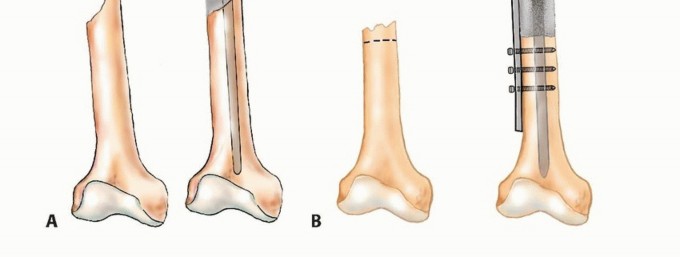

إذا كانت النقيلة قيد الفحص تقع في عظم طويل، فيجب أيضًا إجراء صور أشعة سينية ذات جودة معقولة لكامل امتداد العظم لاستبعاد وجود نقائل إضافية؛ لأن هذه البيانات حاسمة للتخطيط الجراحي. قد تتسبب النقائل التي لم تُكتشف في كسور مرضية عند تحمل الوزن بعد الجراحة وتتطلب جراحة واسعة لإصلاحها.

الشكل 2: أ. صورة أشعة سينية تظهر كسرًا مرضيًا في الورك لدى أنثى تبلغ من العمر 69 عامًا ولديها تاريخ معروف بسرطان الثدي. ب. أجريت عملية استبدال نصفي للورك خلال 24 ساعة من حدوث الكسر، ولكن صور الأشعة السينية بعد الجراحة أظهرت نقيلة إضافية أسفل طرف جذع الطرف الاصطناعي (ج) لم يتم اكتشافها بسبب سوء جودة صور الأشعة السينية قبل الجراحة ولأن صور الأشعة السينية للعظم بالكامل لم تُجرَ قبل الجراحة. د. بينما كانت لا تزال في المستشفى، عانت من كسر مرضي في تلك الآفة أثناء نقلها من سريرها إلى كرسي استلقاء.